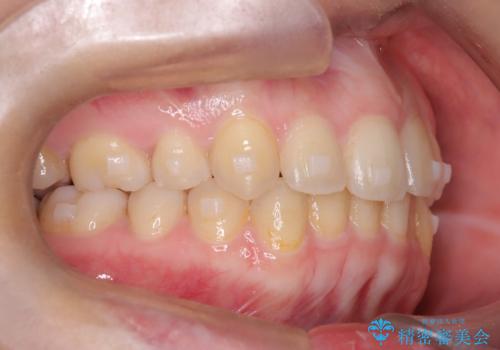

矯正後の後戻り インビザラインで改善

- 20代女性

- 矯正装置

- 治療期間

- 7ヶ月

- 前歯のガタツキが気になると来院されました。

マウスピース矯正治療を選択しました。